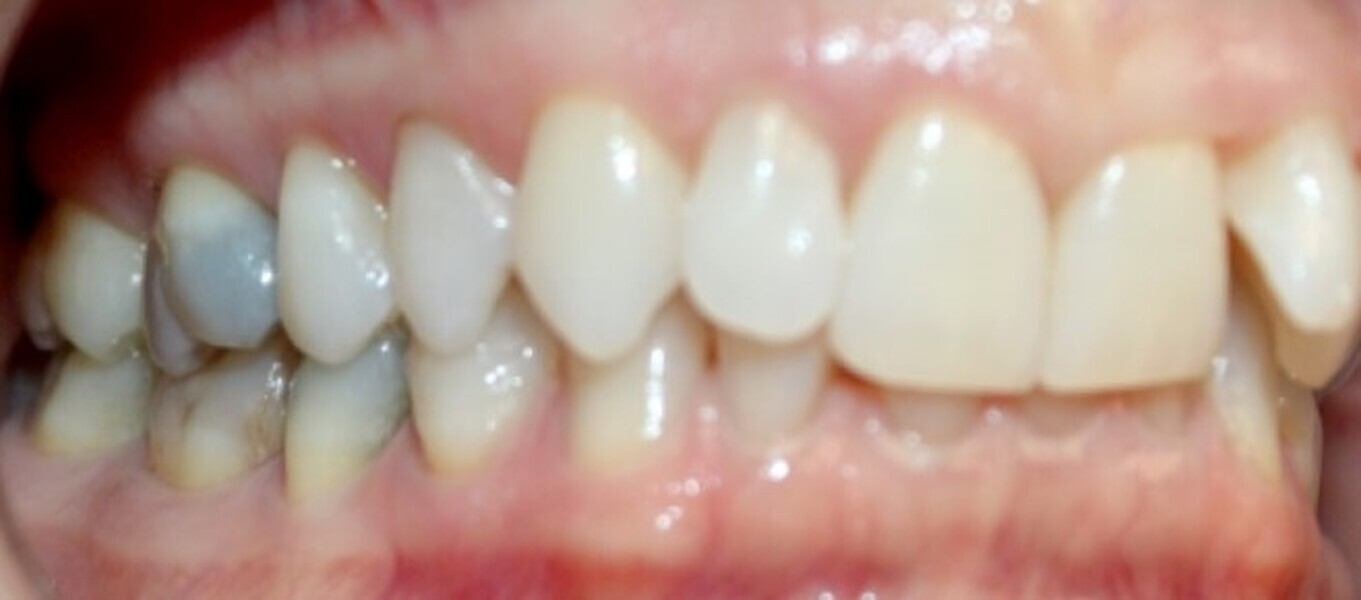

Fig. 18a: Class II malocclusion requiring fixed appliance treatment. (a) Lateral view. (b) Occlusal view.

Fig. 18b: Class II malocclusion requiring fixed appliance treatment. (a) Lateral view. (b) Occlusal view.